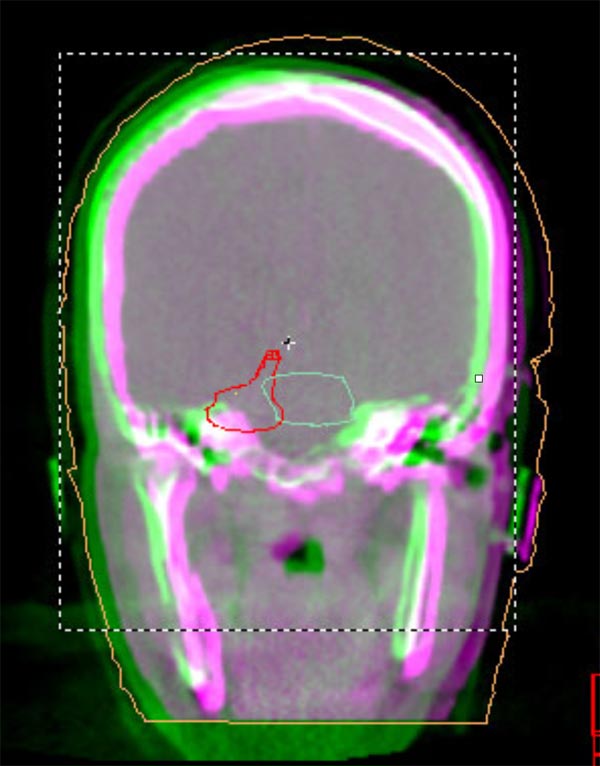

We understand that a cancer diagnosis can be scary, which is why Florida Center For Prostate Care is dedicated to compassionate care and state-of-the-art technology. Florida Center For Prostate Care uses the Elekta Synergy® machine, a digital accelerator for advanced image-guided radiation therapy (IGRT). It is the only all-digital treatment device in the world. This allows your doctor to view your tumor in real-time at the time of your treatment.

The 3-D high-quality images taken at the time of your treatment can be studied against your previous CT scans precisely and promptly to ensure that the doctors are treating your tumor as accurately as possible while greatly limiting any exposure to healthy tissue in the area.

Elekta Synergy® provides unparalleled clinical assurance to more aggressively treat tumors while keeping damage to surrounding healthy tissues to a minimum. Elekta Synergy®‘s precision accuracy reduces or eliminates the use of markers because clinicians can view soft tissue using Elekta Synergy®‘s VolumeViewTM. The low-dose imaging proficiency helps minimize the side effects of radiation therapy by decreasing the margins previously set to account for the unpredictability of target location, movement, and dimensions.